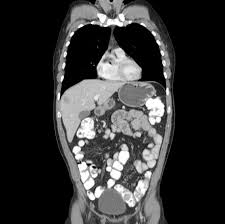

O seu impacto clínico major em idade pediátrica é resultante das complicações associadas à presença de polipos. However this pigmentation may fade over time Presenting symptoms commonly include GI bleeding abdominal pain or intussusception. Peutz-Jeghers syndrome PJS is caused by changes mutations in the STK11 gene. A Sindrome de Peutz-Jeghers é uma rara condição autosómica dominante caracterizada pela associação de polipose gastrointestinal hamartomas pigmentação mucocutânea e risco acrescido de neoplasias em múltiplos órgãos. 1972-06-01 000000 ABSTRACT-A case of Peutz-Jeghers syndrome is presented. Multiple small and large bowel polyps arrows as well as multiple renal angiomyolipomas in left kidney not normally part of the syndrome. Peutz-Jeghers syndrome PJS is a hereditary cancer syndrome characterized by gastrointestinal GI polyposis mucocutaneous pigmented macules and cancer predisposition. Patients with Peutz-Jeghers syndrome are at an increased risk for developing GI cancers of the colorectal pancreatic and gastri. An increased risk of gastrointestinal and nongastrointestinal cancer.

Peutz-Jeghers syndrome PJS Autosomal dominant syndrome characterized by 1. It is clinically characterised by distinct perioral. An increased risk of gastrointestinal and nongastrointestinal cancer. A polypoid jejunal mass was demonstrated angiographically. Patients with Peutz-Jeghers syndrome are at an increased risk for developing GI cancers of the colorectal pancreatic and gastri. Peutz-Jeghers syndrome PJS is a rare autosomal dominant disease linked to a mutation of the STK 11 gene and is characterized by the development of benign hamartomatous polyps in the gastrointestinal tract in association with a hyperpigmentation on the lips and oral mucosa. 1972-06-01 000000 ABSTRACT-A case of Peutz-Jeghers syndrome is presented.